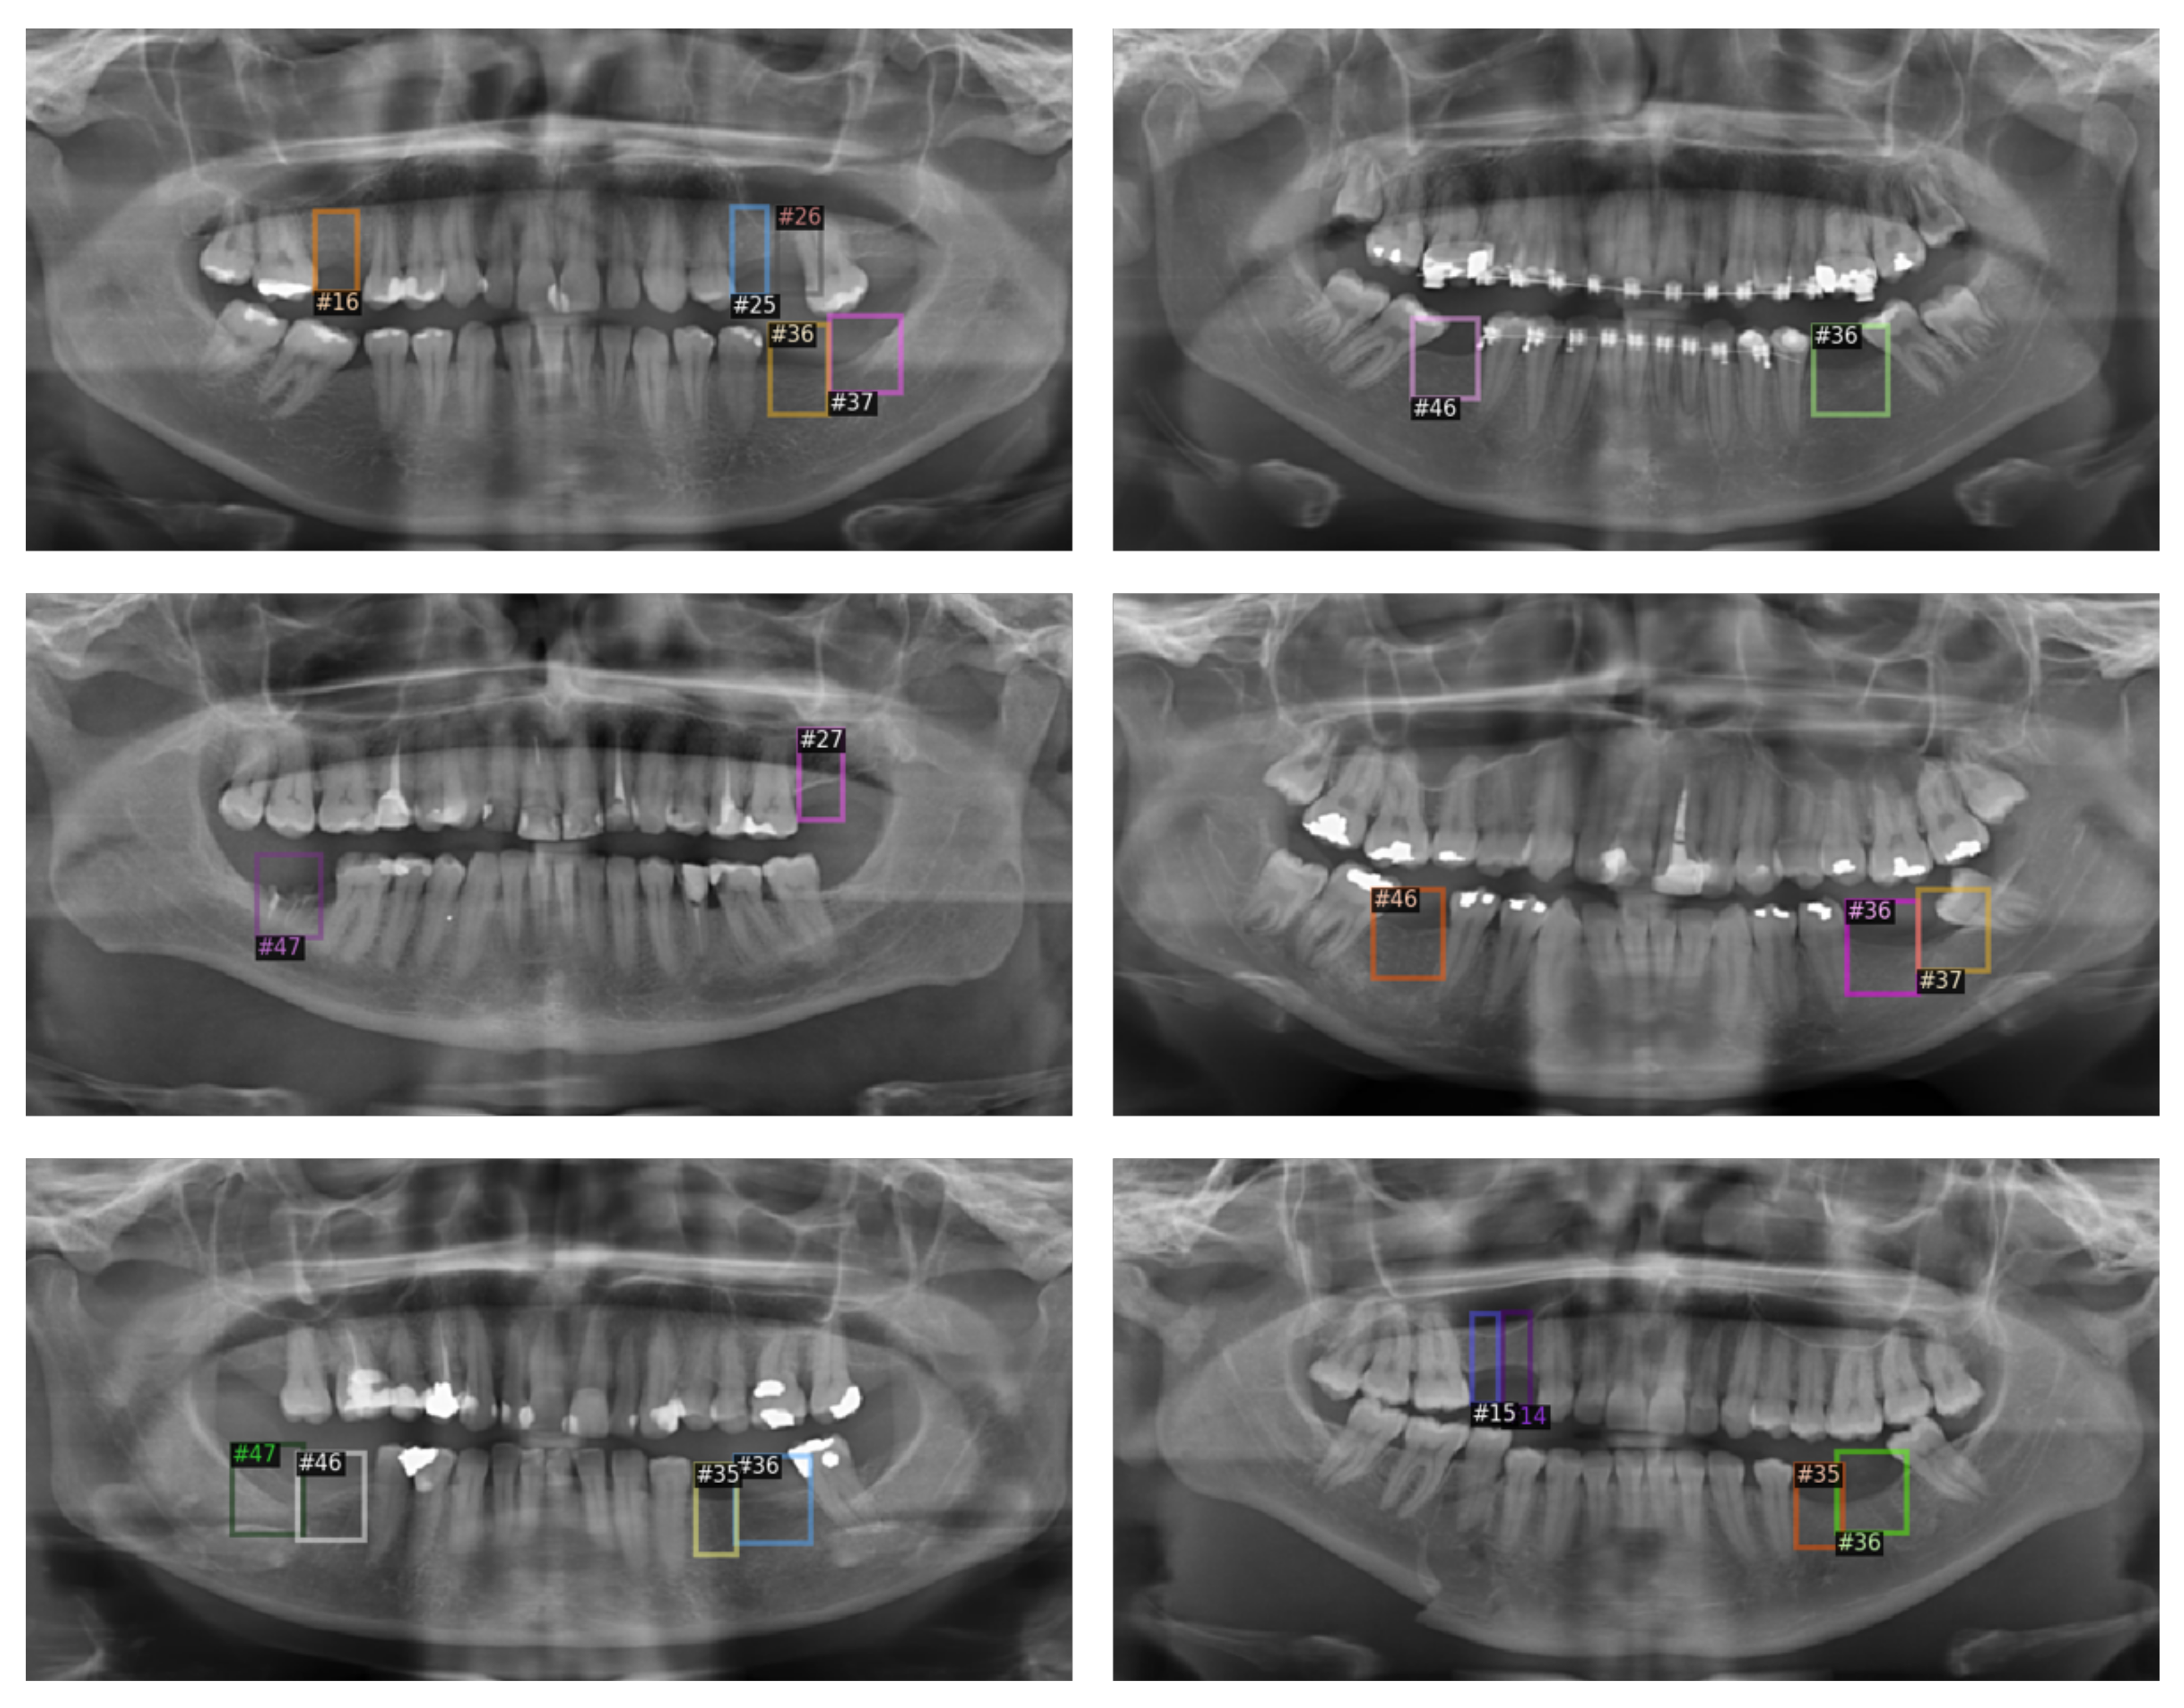

3.2. Missing Tooth Regions Detection Model

| #N | AP (0.5) | #N | AP (0.5) | #N | AP (0.5) | #N | AP (0.5) |

|---|---|---|---|---|---|---|---|

| #11 | 50.95% | #21 | 50.49% | #31 | - | #41 | - |

| #12 | - | #22 | 50% | #32 | - | #42 | - |

| #13 | 100% | #23 | 66.99% | #33 | - | #43 | - |

| #14 | 46.73% | #24 | 63.99% | #34 | 100% | #44 | 0% |

| #15 | 67.82% | #25 | 70.26% | #35 | 73.88% | #45 | 82.26% |

| #16 | 38.5% | #26 | 74.32% | #36 | 91.11% | #46 | 89.74% |

| #17 | 32.53% | #27 | 26.51% | #37 | 27.50% | #47 | 37.77% |